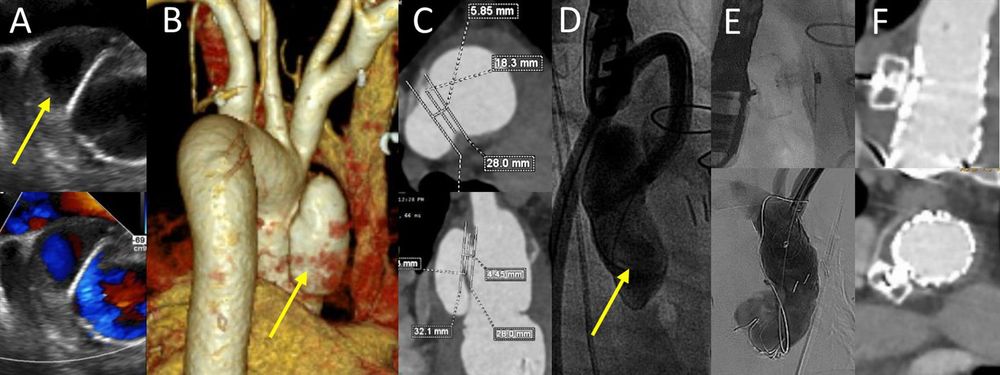

🫀 Major progress! Pre-distance assessment from radial to lower extremity arterial lesion at #IJCVI.

🌐

Pre-distance assessment from radial artery to lower extremity arterial lesion

The International Journal of Cardiovascular Imaging - Endovascular treatment (EVT) for patients with lower extremity artery disease is widely used as a less invasive alternative to surgical bypass....

doi.org